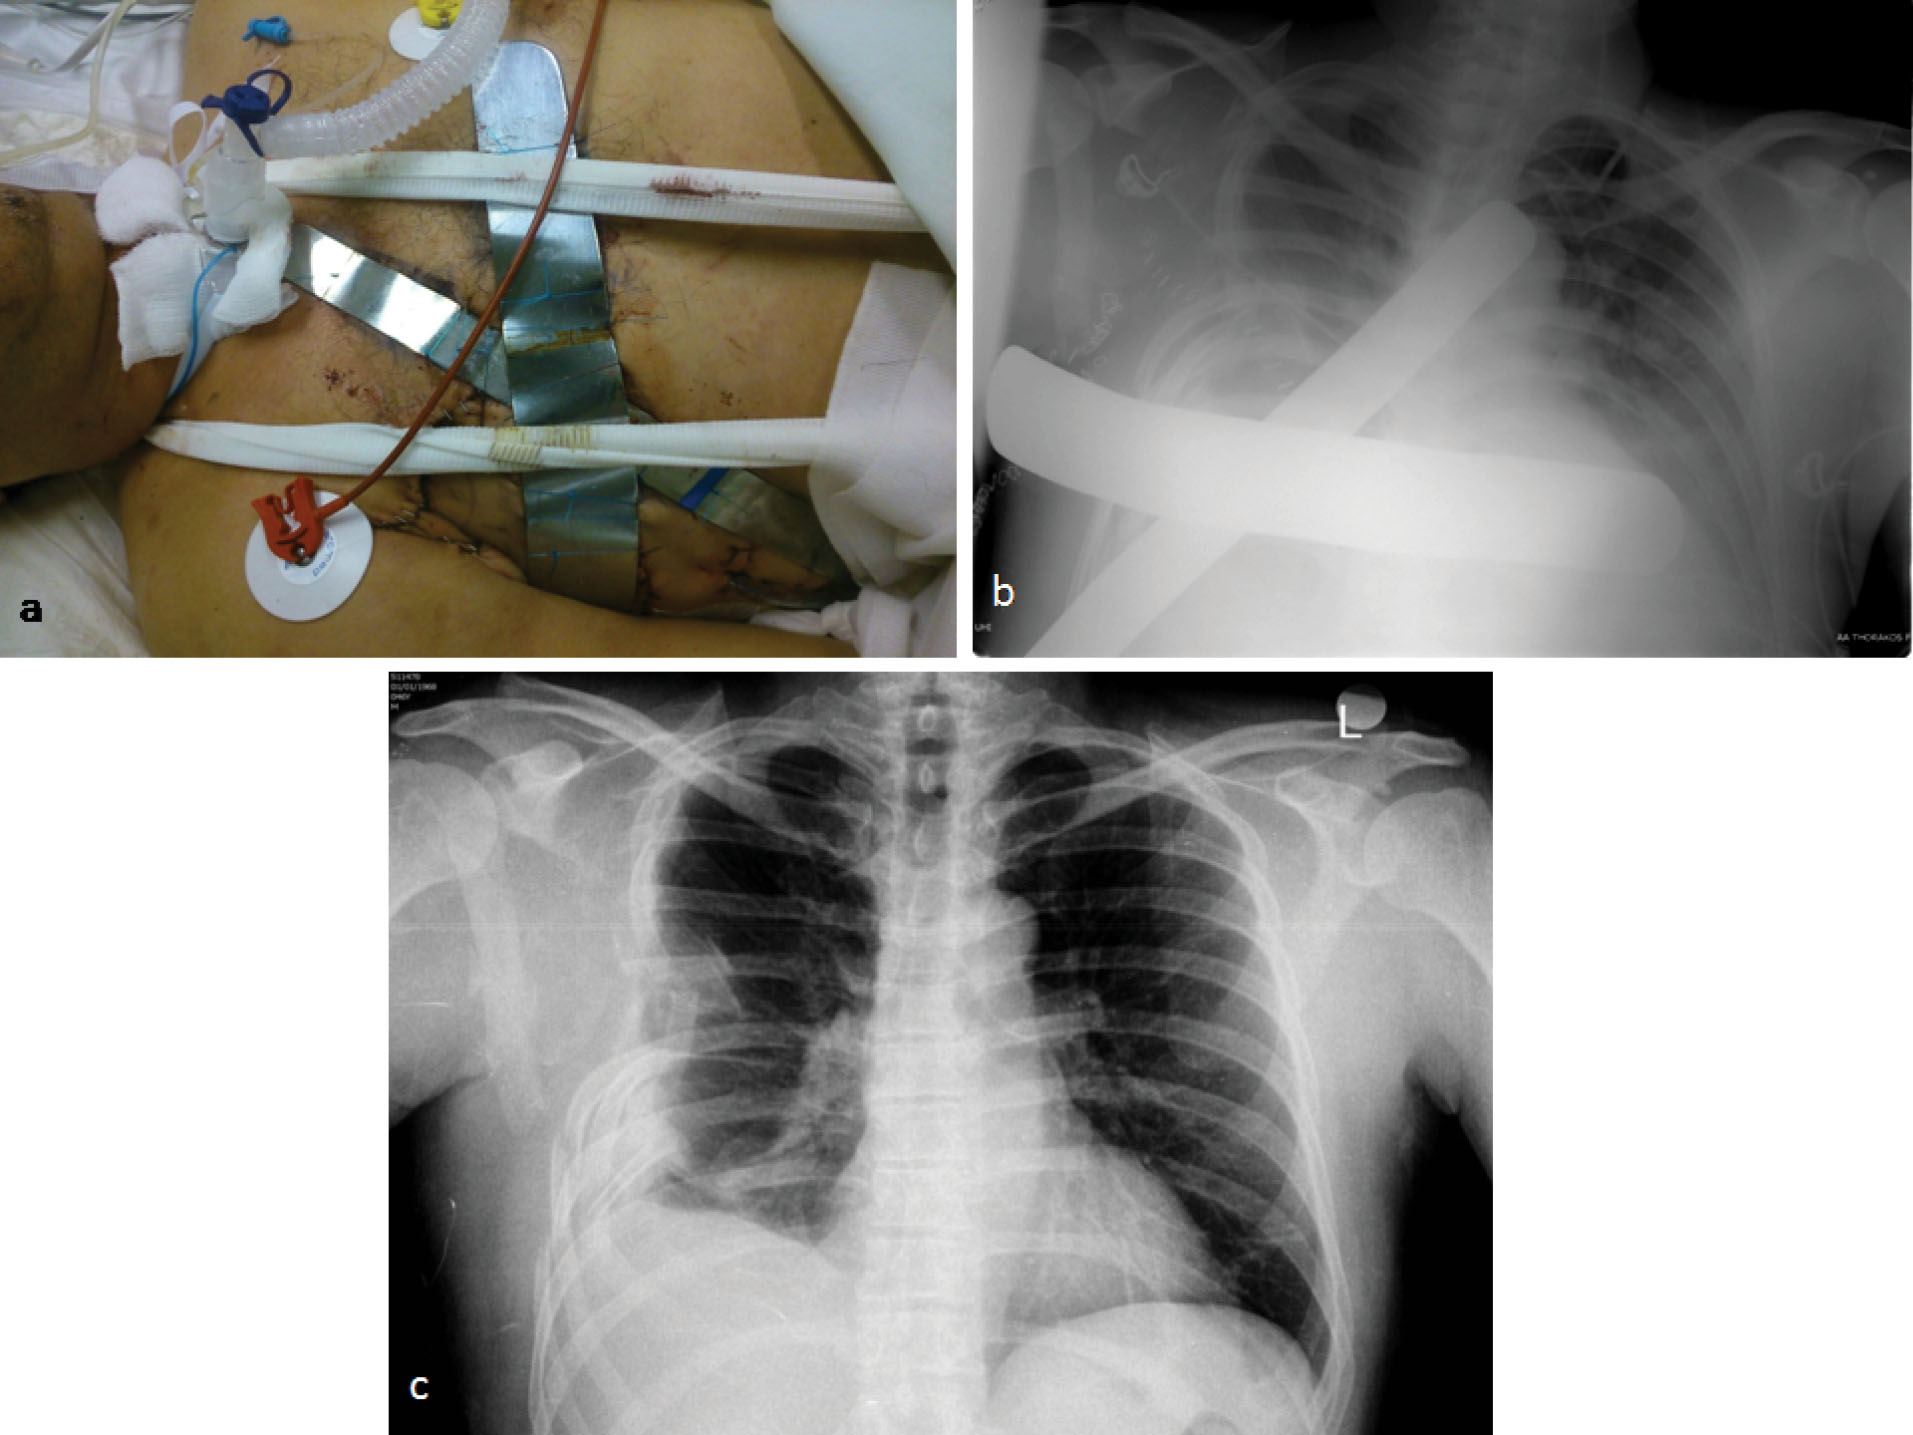

A 58-year-old patient, who was an excavator operator, was crashed down by the bucket of the excavator during work time. His injury resulted in right ribs comminuted fractures and in three infected penetrating traumas of his right anterolateral chest wall. The patient was transferred to hospital having hypoxia and air and blood leak from open wounds, though being hemodynamically stable (blood pressure=110/65 mm Hg, heart rate = 90 beats per minute (bpm)). Physical examination proved neither additional injuries nor any change in Glasgow Coma Scale. Chest x-ray showed right pneumothorax and hemothorax, severe pulmonary contusion of the right lung and multiple rib fractures from the second rib to the eighth one (). Subsequently, a chest tube was placed in his right hemithorax. Arterial blood gases showed severe hypoxia (PO2 = 58 mm Hg, PCO2 = 31 mm Hg, SatO2 = 88%). The patient was intubated and transferred to the operating theatre, where the presence of rib fractures from the second to the eighth rib and of three lung rupture sites with massive air leak were noticed. Debridement of chest wall traumas, suturing of lung rupture sites with a continuous 4-0 Prolene suture through a right lateral thoracotomy and drainage of right pleural cavity via a wide chest tube were performed (). During next postoperative week, the patient presented serious hypoxia and paradoxical motion of the anterolateral chest wall. Despite ventilatory support with FiO2 of 70%-80% and positive end expiratory pressure of 15 mm Hg, patient’s oxygenation was affected (PO2 = 62 mm Hg, PCO2 = 36 mm Hg, SatO2 = 90%) and his extubation was impossible. Consequently, stabilization of chest wall was decided on the seventh postoperative day. After patient’s sedation, two reusable malleable, metallic bars, 25 and 30 centimeters long were chosen and sutured crosswise, so as complete contact with the mobile part of the anterolateral chest wall to be achieved. Multiple non-ischemic, interrupted, 2-0 Nylon sutures were used suturing the bars on the patient’s skin and subcutaneous layer and between them. The edges of metallic bars were sutured on the adjacent normal, stable chest wall resulting in apparent limitation of paradoxical motion (). After chest wall stabilization, arterial blood gases were clearly improved. (PO2 = 75 mm Hg, PCO2 = 36 mm Hg, SatO2 = 96%) Respiratory function improved, hypoxia regressed and the patient was successfully extubated on the third post-stabilization day having satisfactory air blood gases and chest x-ray (). Lung contusion resolution along with mechanical stabilization of the chest were probably the contributors of this achievement. External metallic bars were removed on the ninth post-stabilization day, without any sign of skin necrosis, by simply dividing the stabilizing non-ischemic sutures. The patient was discharged on the 16th post-stabilization day in good health condition without paradoxical motion of his chest wall (). An informed consent was obtained from the patient for the publication of this data.

Figure 1. Chest x-ray and Computed Tomography on patient’s admission Chest x-ray on admission on the left and Computed Tomography imaging of patient’s thorax on the right after his first operation on the right showing pneumothorax (blue arrows) and hemothorax (red arrow) of his right hemithorax, severe pulmonary contusion (red dotted arrow) of his right lung, subcutaneous emphysema and multiple rib fractures from the second rib to the eighth one.(red bracket) A chest drainage tube is in place on the CT image (blue dotted arrow)